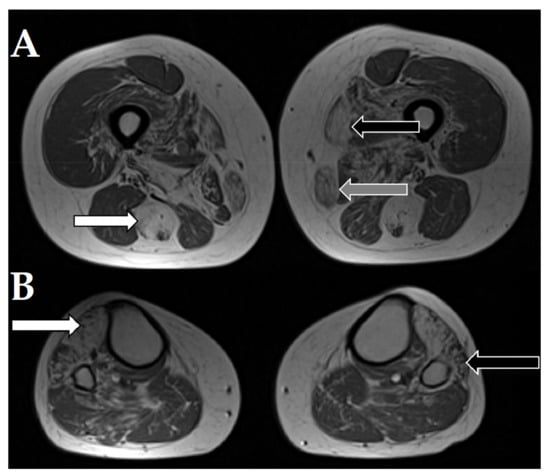

| Muscle MRI: severe symmetric changes in the iliopsoas, semitendinosus, and tibialis anterior muscles and slightly less pronounced abnormalities in the sartorius, gracilis, adductor magnus, short head of the biceps femoris, vastus, and gluteus muscles. | |||||||||

| Muscle MRI: absence of the semimembranosus muscle, severe fatty infiltration in the cervical and thoracic paraspinal, serratus anterior, and gluteus maximus muscles, moderate changes in the adductor magnus, sartorius, vastus lateralis, and gastrocnemius muscles and sternocleidomastoid muscle atrophy | |||||||||

| 8a | recessive SELENON | M | 3 mths | floppy baby syndrome, motor development delay, dysphagia | Moderate weakness: proximal > distal, upper < lower rigid spine, dysmorphic myopathic face, high arched palate, wadding gait | Not on heels | 114 | Myopathic | Chronic respiratory failure after pneumonia at age 4 noninvasive ventilation (BiPAP) required during the night. |

| Muscle MRI: absence of the semimembranosus muscle, severe fatty infiltration in the cervical paraspinal, serratus anterior, gluteus maximus, and sartorius muscles, moderate changes in the thoracic paraspinal, latissimus dorsi, pectoralis major, rotator cuff, adductor magnus, vastus lateralis, biceps femoris, semitendinosus, and gastrocnemius muscles and SCM atrophy | |||||||||